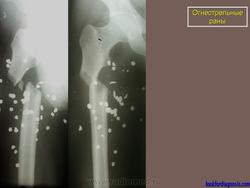

Огнестрел и военные действия.

1.pul_.36.i.slayd35.jpg2.pul_.37.i.slayd36.jpg3.pul_.9.pul_.slayd68.jpg4.pul_.8.pul_.slayd67.jpg5.pul_.7.pul_.slayd66.jpg6.pul_.5.pul_.slayd64.jpg7.pul_.4.pul_.slayd63.jpg7.pul_.6.pul_.slayd65.jpg8.pul_.3.vz_.slayd41.jpg9.pul_.3.pul_.slayd62.jpg